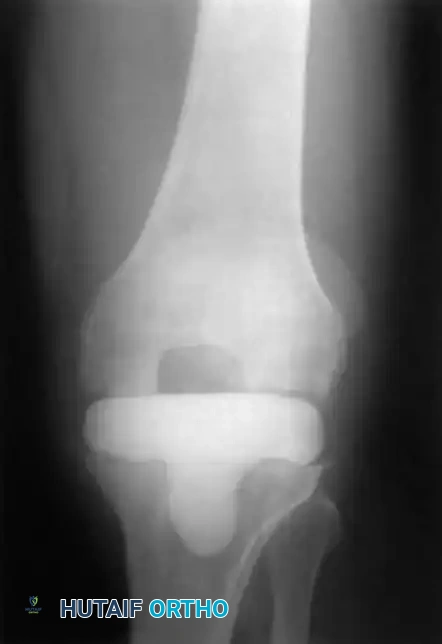

Two-Stage Revision Arthroplasty

The gold standard for chronic PJI.

* Stage 1: Explantation of components, radical debridement, and placement of an antibiotic-impregnated cement spacer.

* Stage 2: After 6-8 weeks of IV antibiotics and normalization of inflammatory markers, the spacer is removed, and revision components are implanted.

Complex two-stage revision TKA utilizing diaphyseal engaging stems and metaphyseal augments to manage severe bone loss.